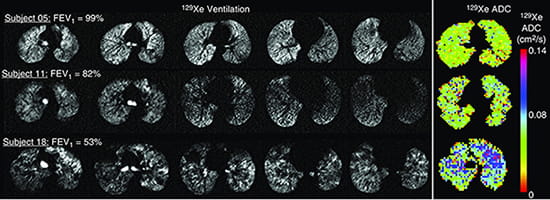

Hyperpolarized Xe gas is emerging as an inhaled contrast agent of assessing pediatric lung disease, and our group is working to improve all aspects of Xe MRI including engineering solutions for faster Xe gas production with higher MRI signal, designing MRI pulse sequences for faster acquisition with shorter breath-holds, and adapting Xe MRI techniques for younger children.

Our team was the first to demonstrate Xe MRI was safe in children and feasible even in children who are unable to perform spirometry, the clinical gold-standard test for lung disease. We recently demonstrated that Xe gas-transfer MRI, a technique that provides regional measurement of pulmonary gas exchange in adults, was feasible in pediatric populations and detected membrane-uptake and red-blood cell transfer abnormalities in children with lung disease.